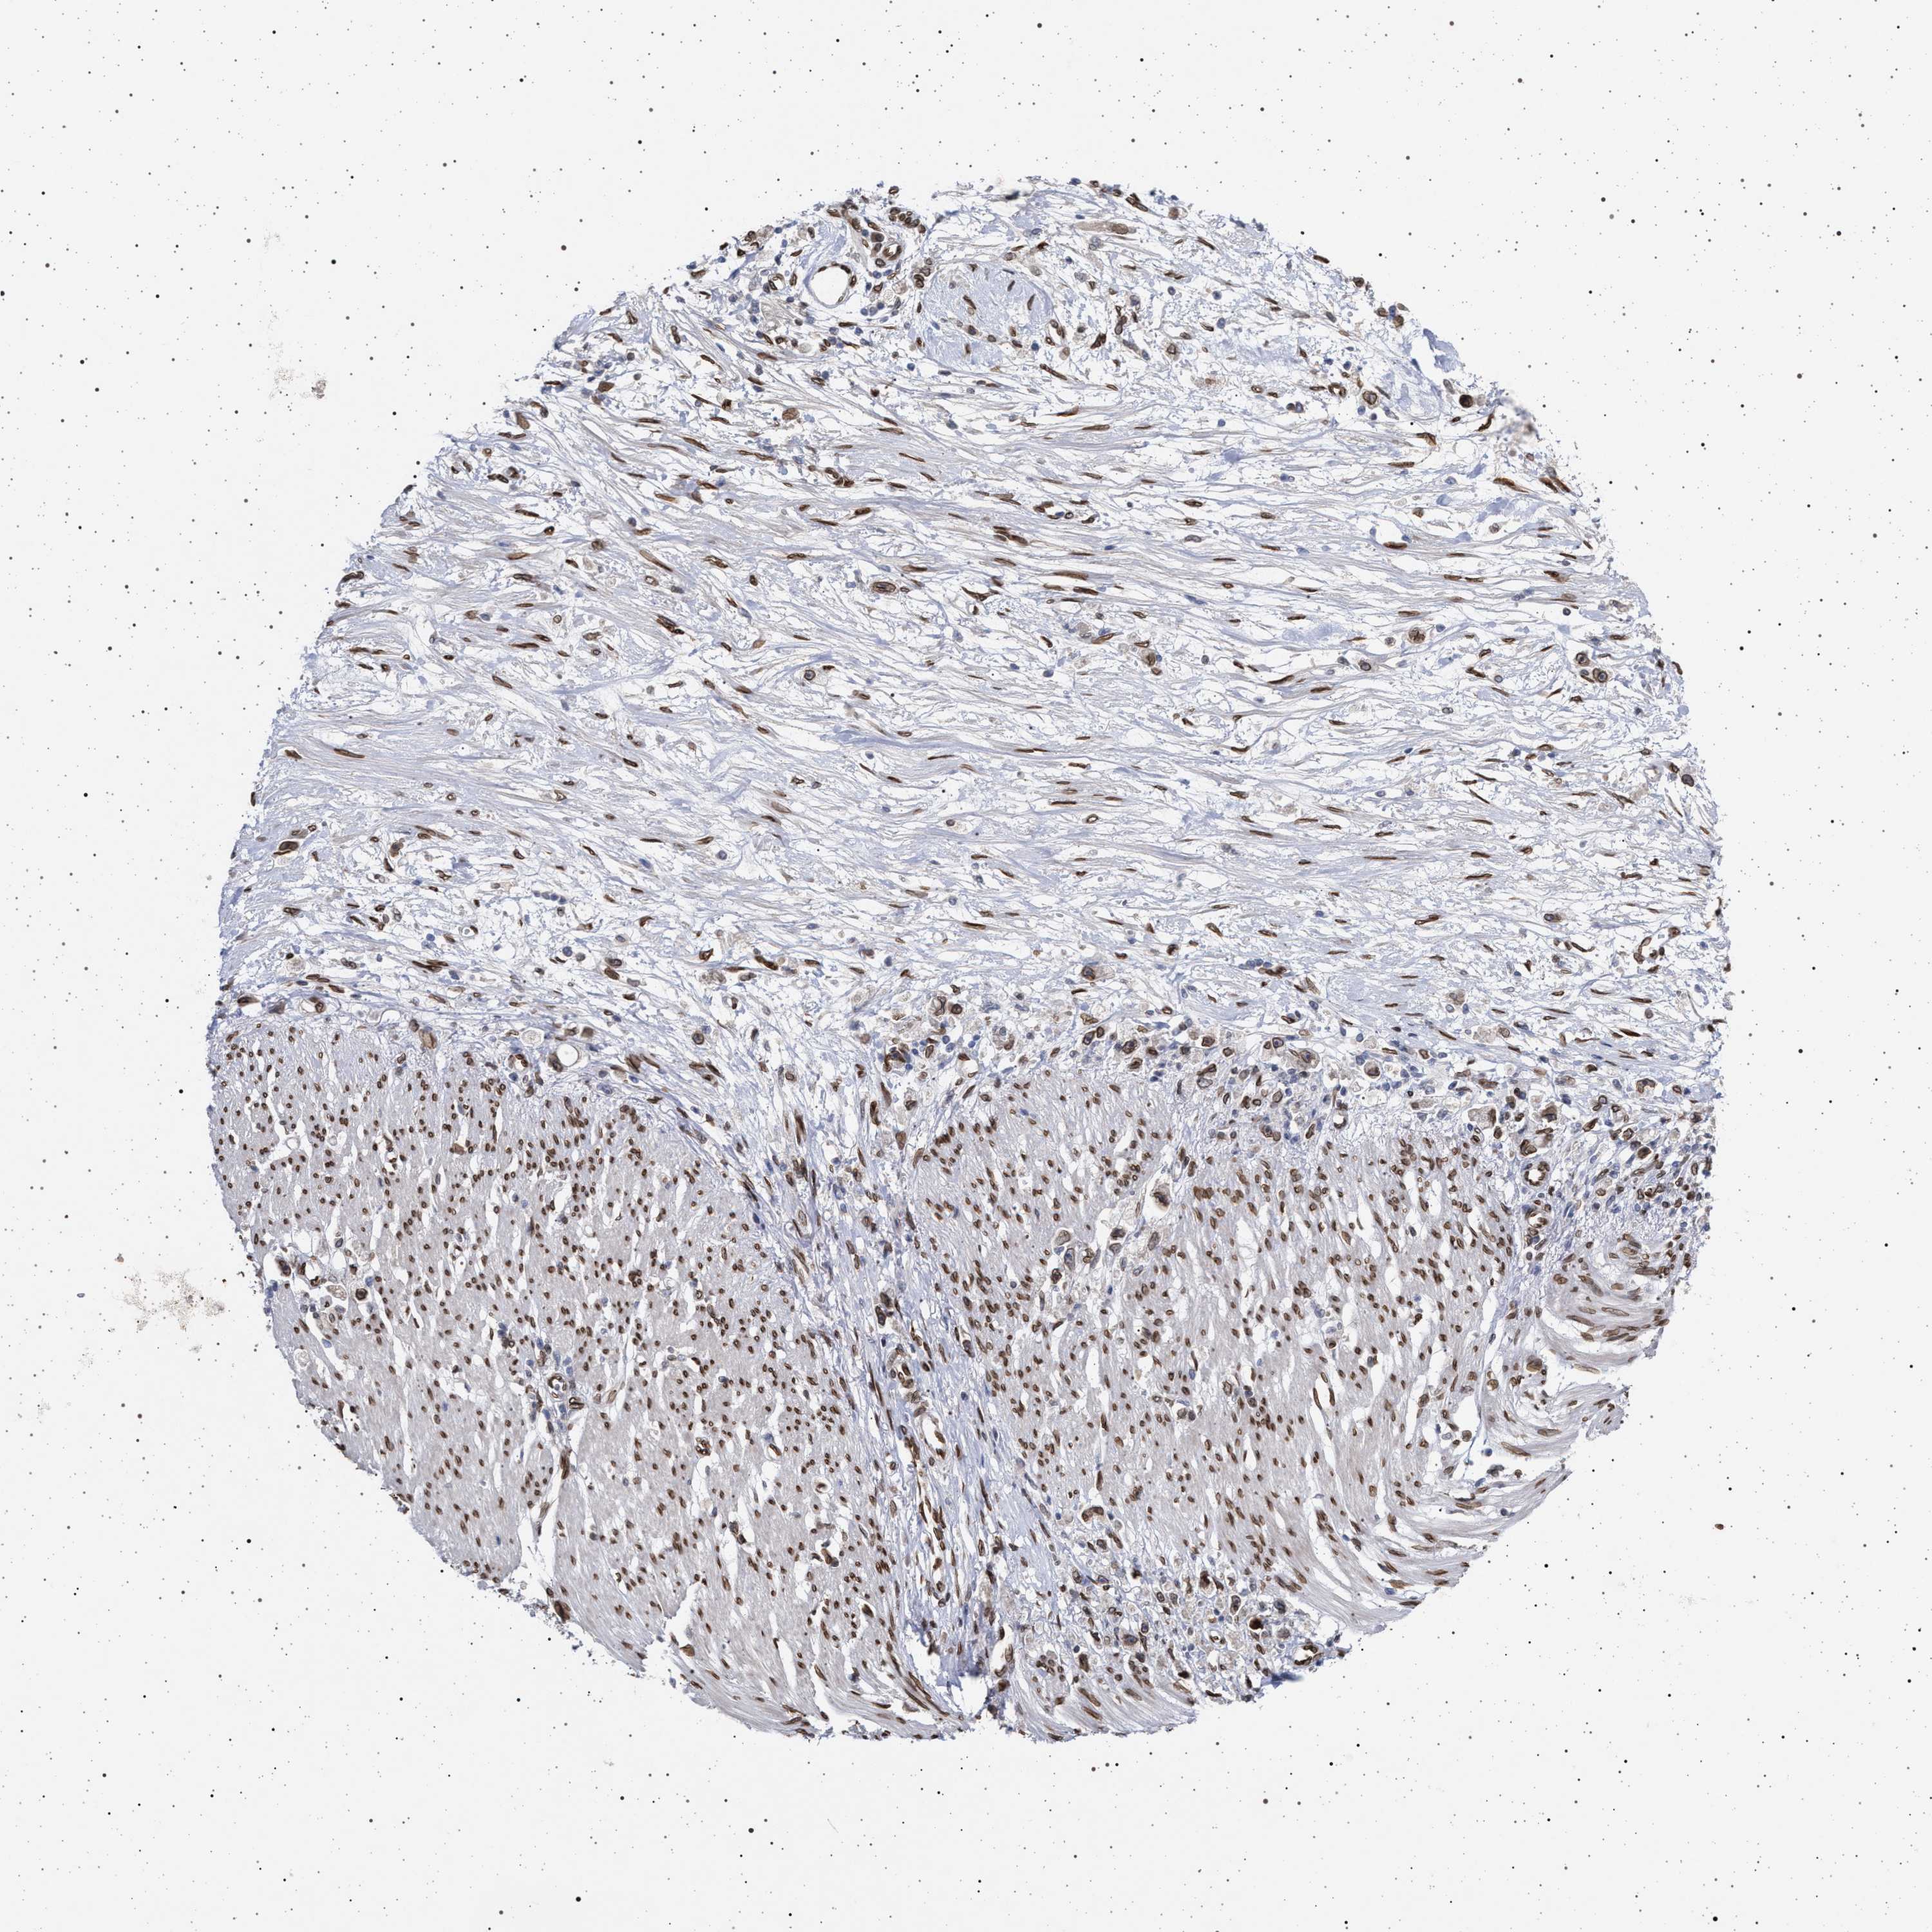

STOMACH CANCER - Protein expressioni

A mouse-over function shows sample information and annotation data. Click on an image to view it in a full screen mode. Samples can be filtered based on level of antibody staining by selecting one or several of the following categories: high, medium, low and not detected. The assay and annotation is described here.

Antibody stainingi

Antibody staining in the annotated cell types in the current human tissue is reported as not detected, low, medium, or high, based on conventional immunohistochemistry profiling in selected tissues. This score is based on the combination of the staining intensity and fraction of stained cells.

Each image is clickable and will lead to virtual microscopy that enables deeper exploration of all samples and also displays staining intensity scores, fraction scores and subcellular localization as well as patient and tissue information for each sample.

Antibody HPA019486

Antibody HPA021517

Staining

High

Medium

Low

Not detected

Intensity

Strong

Moderate

Weak

Negative

Quantity

>75%

75%-25%

<25%

None

Location

Nuclear

Cytoplasmic/membranous

Cytoplasmic/membranous,nuclear

Adenocarcinoma, NOS